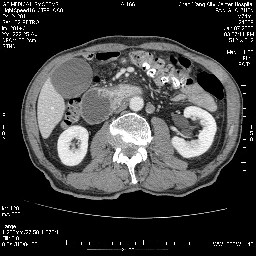

女,74岁,呕吐10余日

考虑来源于十二指肠水平段的恶性占位,侵及周围组织,特别是胰腺,可见区域淋巴结肿大,左侧下腔静脉畸形。

双肾多发小囊肿;左肾积水。

十二指肠水平段腔内占位伴梗阻,中等度较为均匀的强化,洗脱慢,区域淋巴结显示增多,符合腺癌表现。下腔静脉变异。

支持十二指肠腺癌伴梗阻.,下腔静脉发育变异.

十二指肠水平部腺癌伴梗阻并侵犯邻近结构。下腔静脉发育变异。

今日手术结果:胰腺钩突癌侵犯十二直肠,腹腔淋巴结转移.